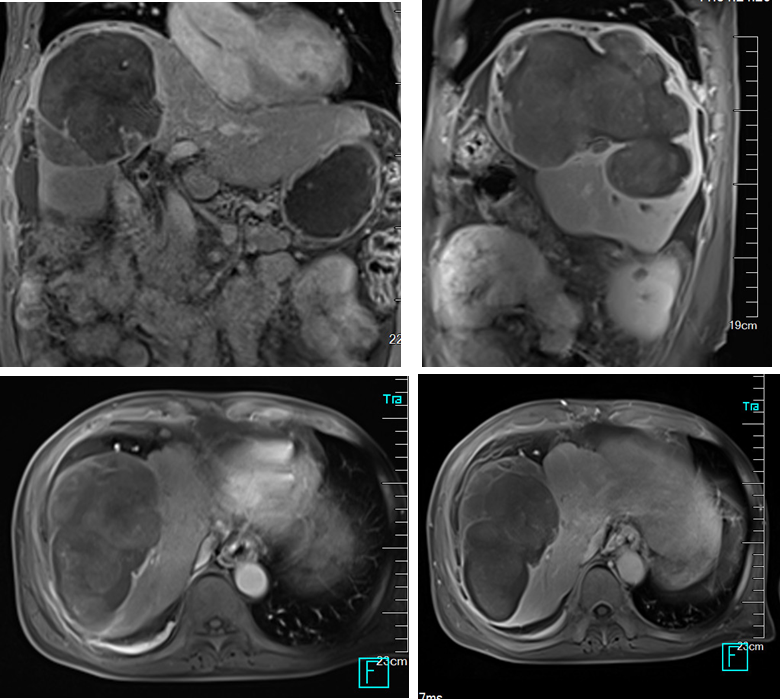

胸部CT未见明确异常,上腹部MRI影像表现:肝脏形态不规则,肝裂增宽,肝实质内可见多发软组织肿块影,呈稍长/稍短T1、稍长T2异常信号,增强扫描动脉期病灶明显、欠均匀强化,门脉期及平衡期强化减低,延迟期见假包膜强化,病灶部分融合,病灶大者11.5cmX18.1cmX14.8cm,肝门及右侧心膈角区可见多发增大淋巴结,大者短径约5mm。

影像诊断:肝内多发占位,考虑原发性肝癌可能性大,并病灶破裂,肝包膜下积血、积液;肝门部及右侧心膈角区多发增大淋巴结;肝硬化、腹水;肝段下腔静脉狭窄。